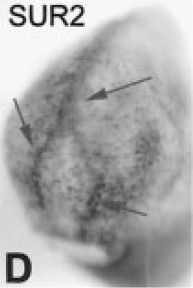

???displayGene.symbol???: abcc9

sur2